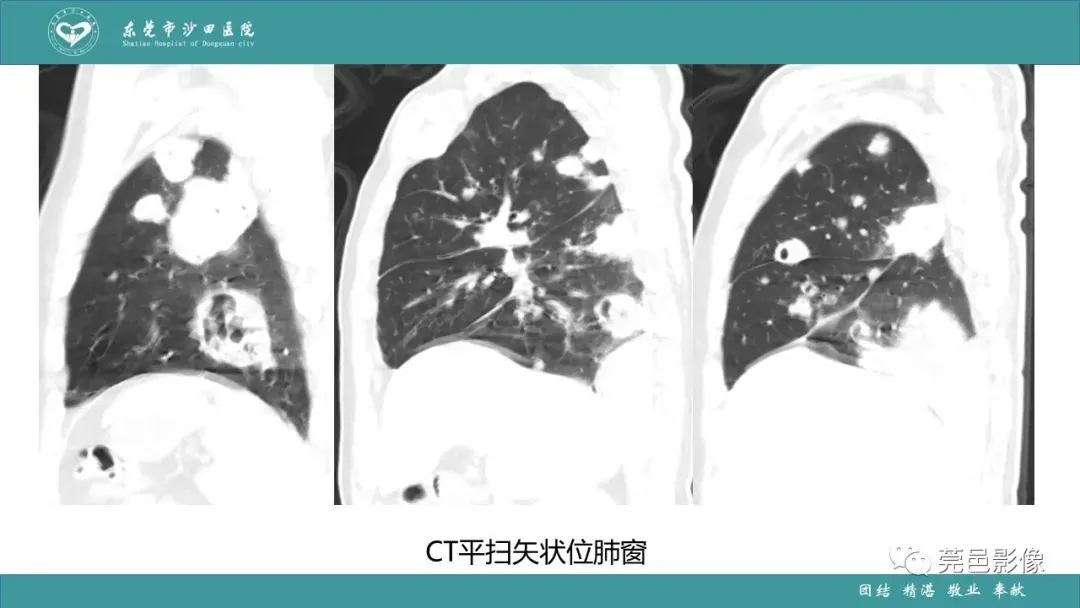

>课件 | 肺炎克雷伯杆菌肺炎影像学诊断与鉴别诊断

课件 | 肺炎克雷伯杆菌肺炎影像学诊断与鉴别诊断